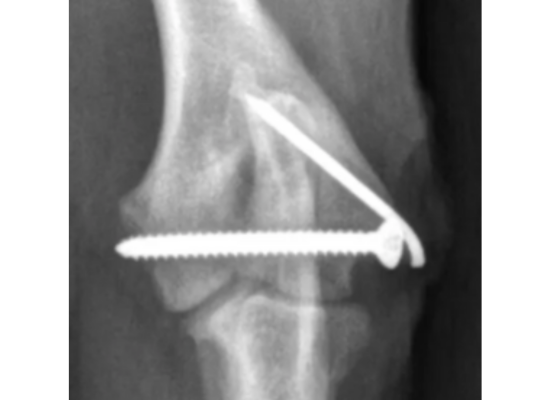

1. Pose de vis transcondylienne

Méthode la plus courante :

une vis est fixée entre les deux condyles pour stabiliser la fissure.

La prise en charge chirurgicale demeure aujourd’hui l’option thérapeutique la plus efficace, avec un excellent pronostic de récupération fonctionnelle. L’intervention consiste le plus souvent en la mise en place d’une vis transcondylienne, pouvant être appliquée en compression afin d’optimiser la stabilité osseuse.Cette vis peut-être mise en place de manière minmallement invasive.

Cette approche chirurgicale réduit significativement le risque de complications ultérieures, notamment en cas d’ossification incomplète ou de fragilité structurelle du condyle huméral. Selon les préférences et l’expertise du chirurgien, il est parfois recommandé d’ajouter une plaque ou une broche au niveau de la crête épicondylaire, renforçant ainsi la fixation et sécurisant davantage la consolidation.